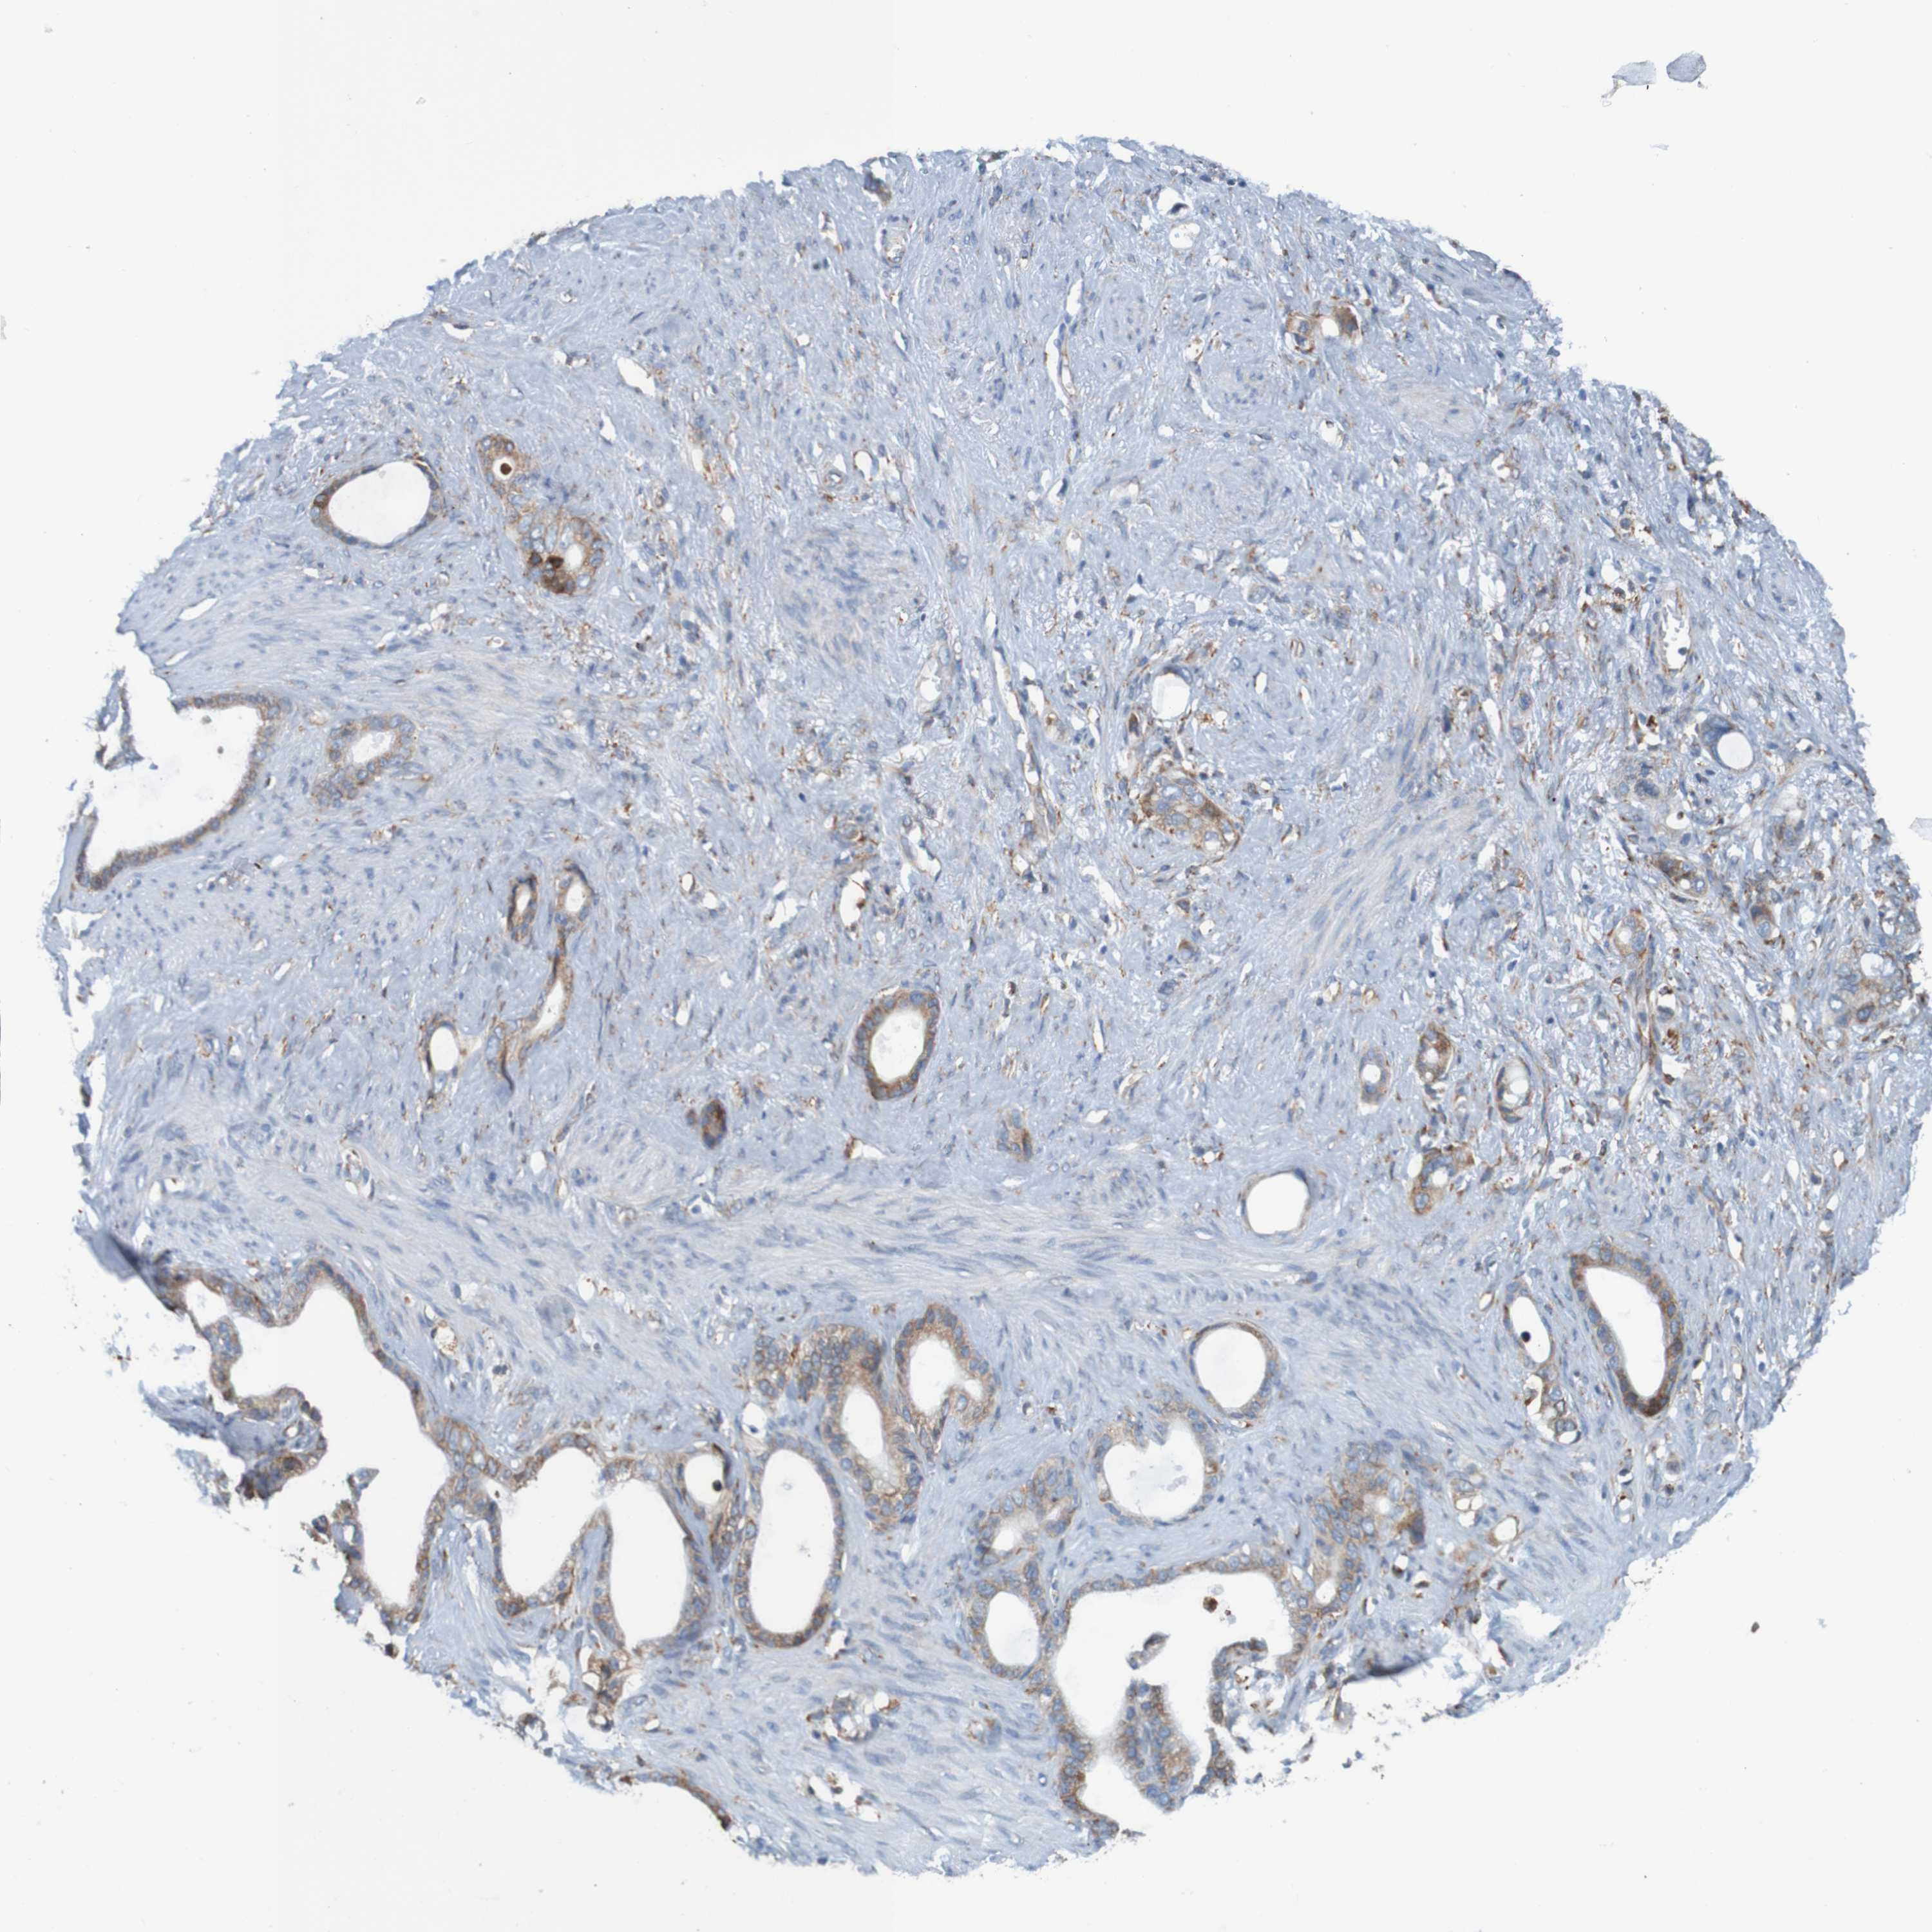

STOMACH CANCER - Protein expressioni

A mouse-over function shows sample information and annotation data. Click on an image to view it in a full screen mode. Samples can be filtered based on level of antibody staining by selecting one or several of the following categories: high, medium, low and not detected. The assay and annotation is described here.

Note that samples used for immunohistochemistry by the Human Protein Atlas do not correspond to samples in the TCGA dataset.

Antibody stainingi

Antibody staining in the annotated cell types in the current human tissue is reported as not detected, low, medium, or high, based on conventional immunohistochemistry profiling in selected tissues. This score is based on the combination of the staining intensity and fraction of stained cells.

Each image is clickable and will lead to virtual microscopy that enables deeper exploration of all samples and also displays staining intensity scores, fraction scores and subcellular localization as well as patient and tissue information for each sample.

Antibody HPA011276

Antibody HPA017062

Staining

High

Medium

Low

Not detected

Intensity

Strong

Moderate

Weak

Negative

Quantity

>75%

75%-25%

<25%

None

Location

Nuclear

Cytoplasmic/membranous

Cytoplasmic/membranous,nuclear

Adenocarcinoma, NOS

Adenocarcinoma, High grade